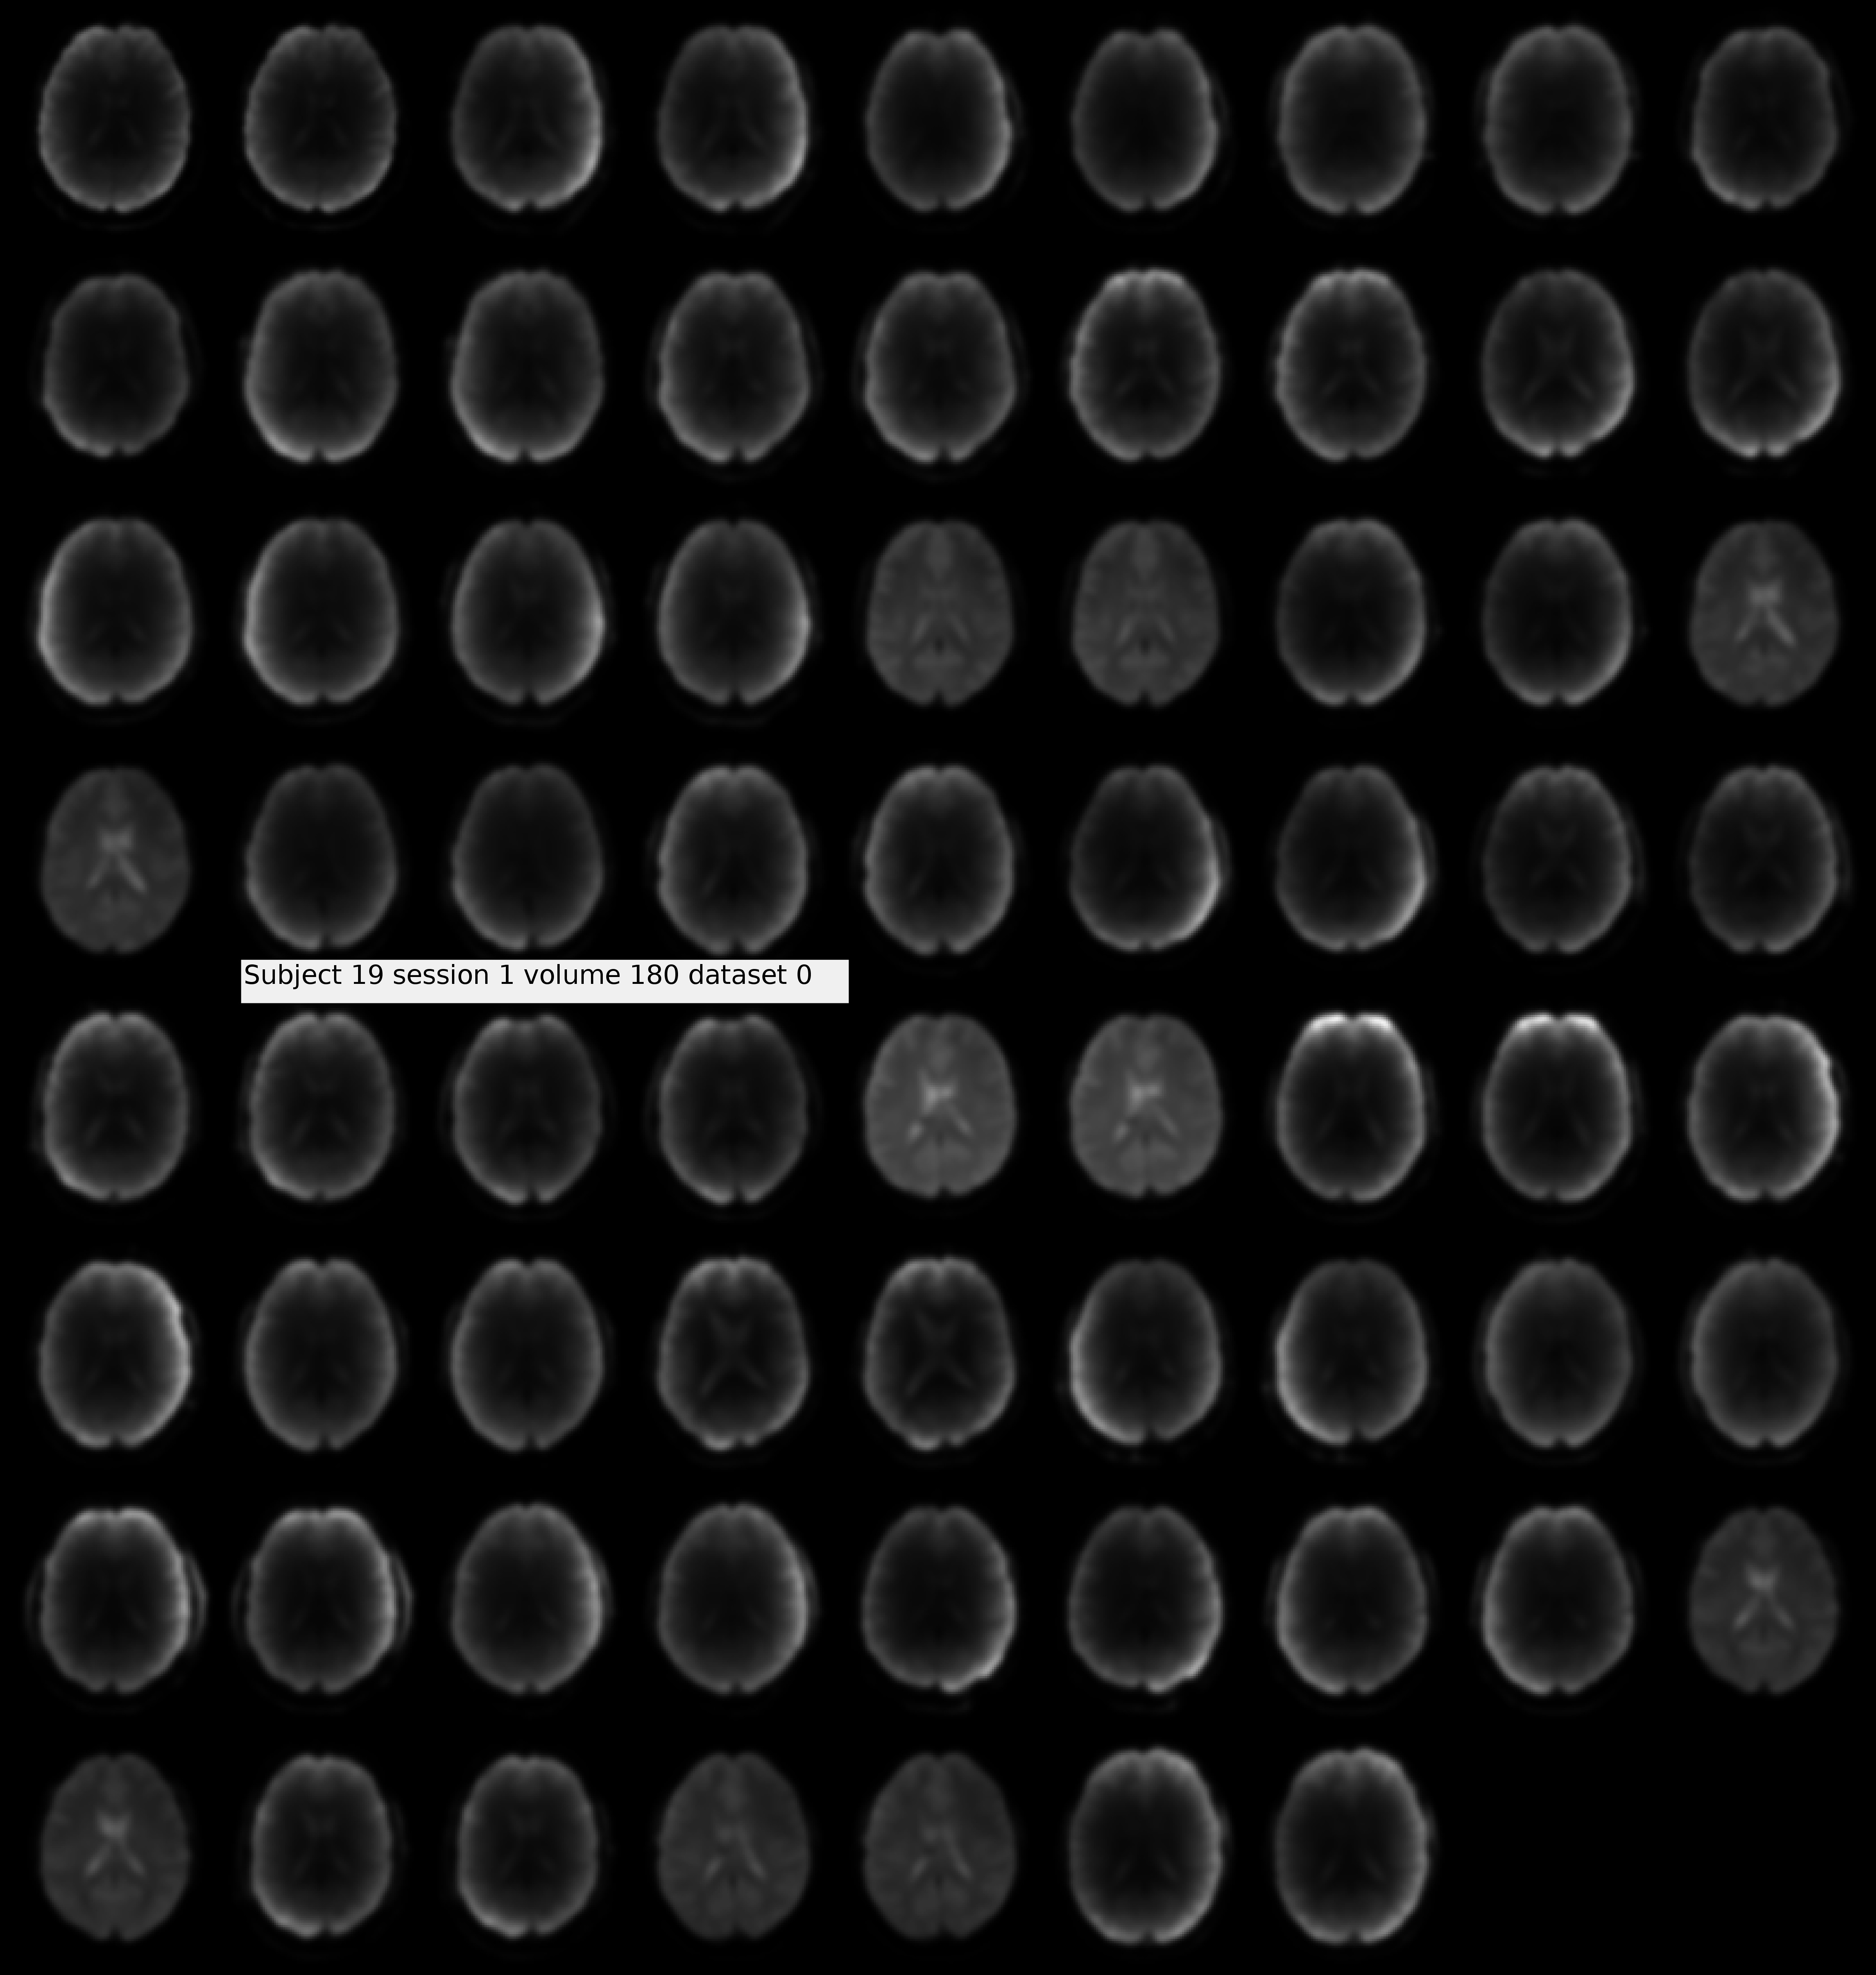

After analyzing and visualizing the functional preprocessed data (montage; attached) of my subjects, I realized most subjects show dark-inside fMRI scans (hollow-resembling) while others do not. Checking their raw fMRI data showed that the "Prescan Normalization" was not active in their acquisition. I wonder whether there is any need for intensity normalization for the fMRI acquisitions, and whether it is done by "denoising" or not. I tried to do that on one of the subjects. Interestingly, before denoising there was a right-leaning skewness in the probability distribution which converts to a normal distribution after that.